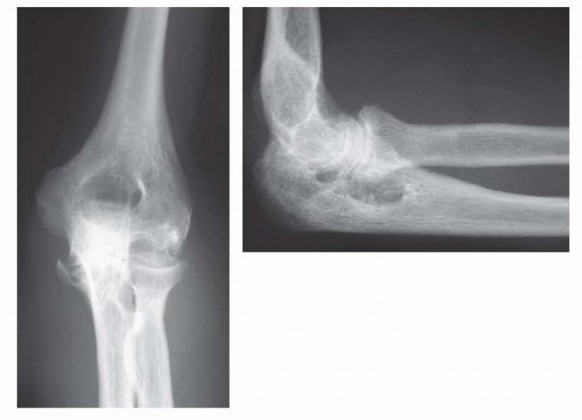

15 MIN READ Surgical Management of Traumatic Conditions of the Elbow: Interposition Arthroplasty يناير 2023 Read More